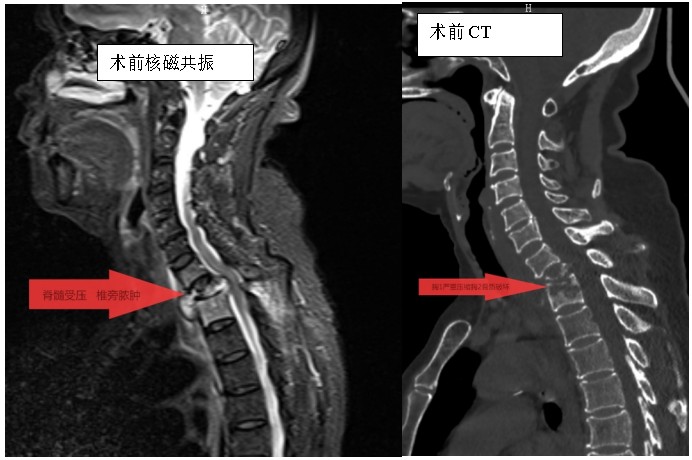

家住耒陽的70歲的李奶奶,因“頸胸背部疼痛不適伴雙上肢麻木6個月”,來到衡陽市中心醫(yī)院脊柱外科住院,住院當(dāng)天,患者頸胸椎核磁共振顯示:胸1、2椎體骨質(zhì)破壞,伴胸1、2椎旁軟組織腫脹、同層面椎管變窄,因脊髓受壓而導(dǎo)致頸胸背部疼痛。在錢軍博士帶領(lǐng)下,醫(yī)療團(tuán)隊詳細(xì)予以完善相關(guān)檢查后,研究患者的臨床資料,考慮脊柱結(jié)核并椎旁膿腫的可能性大,由于患者胸1椎體病理性骨折并椎管狹窄,遂囑患者嚴(yán)格臥床休息,術(shù)前給予標(biāo)準(zhǔn)四聯(lián)抗結(jié)核藥物治療2周,以控制活動性結(jié)核感染,降低術(shù)中播散風(fēng)險,并嚴(yán)密監(jiān)測肝腎功能及血常規(guī)情況。